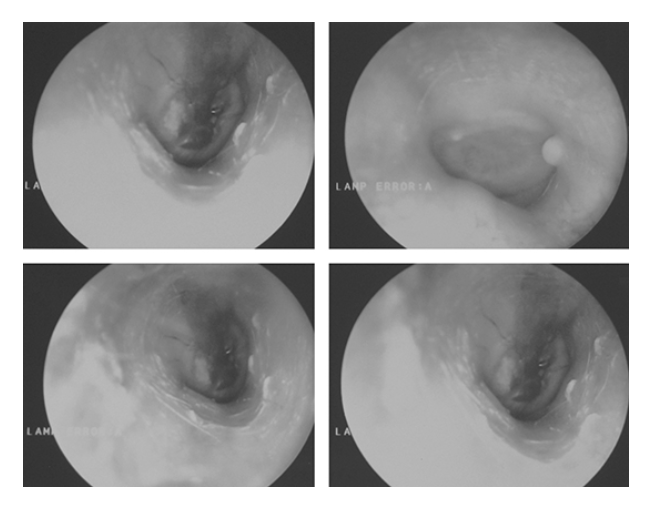

What does the figure show?

Glomus Tumor (Glomus Tympanicum). Clinical otoscopic images show a (blue) vascular mass located behind the eardrum. This corresponds to the mass seen on the cochlear promontory